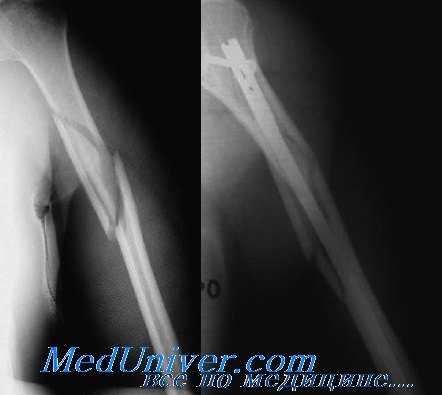

Рентгенограмма при переломе диафиза плечевой кости

(Слева) На боковой и передне-задней рентгенограммах правого плечевого сустава у женщины 62 лет с болью и деформацией после падения с высоты тела виден перелом средней трети диафиза плечевой кости с варусным отклонением >30°. Кроме того, она не могла разогнуть запястье. Пацинтке проведена успешная закрытая репозиция под анестезией, проведенной в связи с парезом лучевого нерва и варусным отклонением.

(Справа) На передне-задней рентгенограмме виден оскольчатый спиральный перелом плечевой кости. Перелом хорошо сросся в гильзовой повязке.